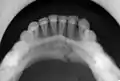

- occlusal radiograph of a mandibular parasymphysis fracture